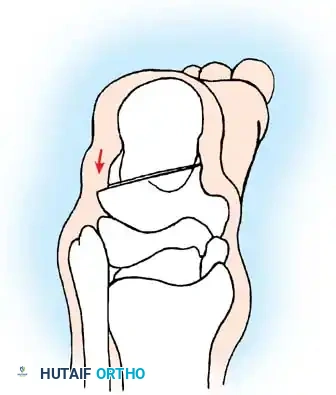

## فهم طبيعة المشكلة وكيفية حدوثها لفهم كيفية حدوث تشوهات القدم في الشلل الدماغي، يجب أن ننظر إلى العلاقة المعقدة بين الأعصاب والعضلات والعظام. في الحالة الطبيعية، تعمل العضلات في أزواج متوازنة (عضلات تشد وأخرى ترخي) لتوجيه حركة المفصل. ولكن في حالة الشلل الدماغي، ترسل الإشارات العصبية غير المنتظمة أوامر مستمرة لبعض العضلات بالانقباض (التشنج)، مما يخلق قوى غير طبيعية وغير متكافئة على عظام ومفاصل القدم. النوع الأكثر شيوعاً من هذه التشوهات هو "القدم الخيلية" أو المشي على أطراف الأصابع، حيث تكون القدم مشدودة لأسفل. وتحدث تشوهات أخرى مثل انحراف القدم للداخل أو انحراف القدم للخارج بنسب متقاربة، وذلك يعتمد بشكل كبير على التوزيع التشريحي للإصابة العصبية لدى الطفل. وقد أثبتت الدراسات الكبرى أن وجود تشوه في القدم، خاصة إذا كان في كلتا القدمين، يؤثر بشكل سلبي وكبير على قدرة الطفل على المشي ويزيد من المجهود البدني المطلوب للحركة مقارنة بالأطفال الذين يعانون من إصابة في قدم واحدة.  ## أسباب وعوامل تطور تشوهات القدم من المهم جداً للآباء أن يدركوا أن تشوهات القدم في الشلل الدماغي نادراً ما تكون ثابتة؛ بل هي تتطور وتتغير ديناميكياً بمرور الوقت، وتحديداً خلال فترات النمو السريع لهيكل الطفل العظمي. تكمن المشكلة الأساسية في أن العظام تنمو بمعدل طبيعي، بينما العضلات المتشنجة والمشدودة (مثل عضلة الساق الخلفية) لا تنمو بنفس السرعة وتفتقر إلى المرونة اللازمة لمواكبة نمو العظام. هذا التفاوت يؤدي إلى قصر نسبي في العضلة والوتر، مما يسحب القدم إلى وضعيات غير طبيعية. على سبيل المثال، قد يبدأ الطفل الصغير بتشوه مرن في القدم، ولكن مع استمرار التشنج العضلي وقوى الشد غير الطبيعية أثناء المشي، قد يتحول هذا التشوه المرن بمرور الوقت إلى تشوه عظمي صلب وتيبس كامل في المفصل. بالإضافة إلى ذلك، فإن تشنج العضلات الدقيقة داخل القدم يمكن أن يؤدي إلى تشوهات ثانوية في الأصابع ومقدمة القدم، مثل انحراف إصبع القدم الأكبر أو التصاق الأصابع. ## الأعراض والعلامات التحذيرية التشوه الأبرز والأكثر شيوعاً هو "القدم الخيلية"، والذي يصيب ما يصل إلى 70% من الأطفال المصابين. وهناك علامات يجب على الآباء الانتباه لها: * المشي المستمر على أطراف الأصابع وعدم القدرة على ملامسة الكعب للأرض. * رجوع الركبة للخلف بشدة أثناء الوقوف أو المشي للتعويض عن قصر وتر أخيل. * صعوبة بالغة في إدخال قدم الطفل في الحذاء العادي. * تآكل الحذاء بشكل غير متساوٍ من جهة معينة. * ألم في القدم أو الساق بعد المشي لمسافات قصيرة. * ظهور تقرحات جلدية في مناطق الضغط غير الطبيعي، خاصة لدى الأطفال الذين يستخدمون الكراسي المتحركة. ## التقييم الطبي والتشخيص يبدأ التقييم الطبي الدقيق بزيارة طبيب جراحة عظام الأطفال المتخصص. سيقوم الطبيب بإجراء فحص سريري شامل لتقييم: * مدى التشنج العضلي في الساق والقدم. * الفرق بين التشوه المرن الذي يمكن تصحيحه باليد، والتشوه الصلب (الثابت). * تحليل نمط مشي الطفل. * إجراء اختبارات خاصة مثل اختبار سيلفرسكيولد لتحديد ما إذا كان الشد ناتجاً عن عضلة الساق العلوية فقط أم يمتد ليشمل وتر أخيل بالكامل. ## الخيارات العلاجية غير الجراحية يعتبر العلاج التحفظي (غير الجراحي) هو خط الدفاع الأول، والهدف الأساسي منه هو الحفاظ على مرونة المفاصل، وتحسين وظيفة القدم، وتأخير الحاجة للتدخل الجراحي قدر الإمكان حتى يكبر الطفل، مما يقلل من احتمالية عودة التشوه. تشمل الخيارات غير الجراحية ما يلي: ### العلاج الطبيعي المكثف يركز العلاج الطبيعي على تمارين الإطالة السلبية للعضلات المتشنجة. وقد أثبتت الأبحاث أن العضلة تحتاج إلى فترات طويلة من الإطالة اليومية لمنع حدوث قصر دائم فيها، وهو ما يتطلب التزاماً كبيراً من الأسرة. ### استخدام الجبائر والأجهزة التعويضية تعتبر الجبائر البلاستيكية الداعمة للكاحل والقدم من أهم أدوات العلاج. وتستخدم الجبائر الليلية الصلبة بشكل خاص للحفاظ على القدم في وضع معتدل ولمواجهة التشنجات التي تزيد أثناء النوم. ### الحقن والجبس المتسلسل يُعد حقن البوتكس في العضلات المتشنجة إجراءً فعالاً لإرخاء العضلة مؤقتاً. وغالباً ما يُتبع الحقن بوضع سلسلة من قوالب الجبس التي يتم تغييرها كل أسبوعين إلى ثلاثة أسابيع لإطالة العضلة تدريجياً وتحسين المدى الحركي للمفصل.  | نوع العلاج التحفظي | الهدف الرئيسي | ملاحظات هامة | | :--- | :--- | :--- | | العلاج الطبيعي | الحفاظ على مرونة العضلات والمفاصل | يحتاج إلى استمرارية والتزام يومي | | الجبائر التقويمية | منع تفاقم التشوه وتثبيت القدم | ضرورية جداً أثناء فترات النوم | | حقن البوتكس | إرخاء العضلات المتشنجة مؤقتاً | تأثيره يستمر لعدة أشهر ويساعد في تأخير الجراحة | | الجبس المتسلسل | إطالة الأوتار تدريجياً | يستخدم غالباً بالتزامن مع حقن البوتكس | ## دواعي التدخل الجراحي لتشوهات القدم يصبح التدخل الجراحي ضرورياً عندما تفشل الطرق التحفظية في السيطرة على التشوه، أو عندما يصبح التشوه ثابتاً ويعيق حياة الطفل. تختلف دواعي الجراحة بناءً على قدرة الطفل على المشي: **للأطفال القادرين على المشي:** يتم اللجوء للجراحة عند عدم قدرة الطفل على وضع كاحله في زاوية قائمة أثناء المشي مع فرد الركبة، مما يؤدي إلى المشي على أطراف الأصابع، أو التواء الركبة للخلف، أو رفع الكعب مبكراً أثناء المشي. **للأطفال غير القادرين على المشي:** تُجرى الجراحة لتخفيف التقلصات الشديدة التي تمنع ارتداء الأحذية، أو تعيق برامج الوقوف المدعوم، أو تتسبب في تقرحات جلدية وصعوبات في النظافة الشخصية. > **تحذير جراحي بالغ الأهمية خطر الإطالة المفرطة** > يجب على الجراح توخي الحذر الشديد لتجنب الإطالة المفرطة لوتر أخيل أو عضلة الساق، خاصة لدى الأطفال الذين يمشون. الإطالة الزائدة تدمر القوة الدافعة للقدم وتؤدي إلى تطور ما يُعرف بـ "مشي القرفصاء". هذا النمط من المشي كارثي من الناحية الميكانيكية، حيث يؤدي إلى إرهاق سريع لعضلات الفخذ الأمامية وفقدان القدرة على المشي المستقل.  ## عمليات تطويل وتر أخيل نظراً لاختلاف حالات الشلل الدماغي، توجد تقنيات جراحية متعددة لتصحيح تشوه القدم الخيلية. تعتمد نسبة نجاح العملية وعدم عودة التشوه بشكل كبير على عمر الطفل وقت الجراحة ونوع الشلل الدماغي. تشير الدراسات إلى أن إجراء الجراحة بعد سن السادسة يقلل بشكل كبير من احتمالية عودة التشوه مقارنة بإجرائها في سن مبكرة جداً. يمكن إطالة مجمع عضلة الساق ووتر أخيل في مستويين رئيسيين: إما عند اتصال العضلة بالوتر، أو في وتر أخيل نفسه. ### التطويل المفتوح لوتر أخيل تُستخدم هذه التقنية (وتعرف بتعديل وايت) وتعتمد على الانزلاق الطبيعي لألياف وتر أخيل التي تلتف حول نفسها بطبيعتها التشريحية.  **خطوات العملية الجراحية:** * يتم عمل شق جراحي طولي خلف الكاحل للوصول إلى الوتر. * يقوم الجراح بعمل قطع جزئي في الجزء السفلي من الوتر، وقطع جزئي آخر في الجزء العلوي في اتجاه معاكس. * عندما يتم دفع القدم بلطف إلى الأعلى (نحو الساق)، تنزلق ألياف الوتر المقطوعة فوق بعضها البعض، مما يؤدي إلى زيادة طول الوتر للمستوى المطلوب لتصحيح التشوه. * تتميز هذه الطريقة بالحفاظ على الغلاف المحيط بالوتر لمنع الالتصاقات.   بعد العملية، يتم وضع قدم الطفل في جبس قصير يمتد تحت الركبة لمدة 4 أسابيع، ويُسمح للطفل بالمشي عليه. بعد إزالة الجبس، يتم استخدام جبيرة بلاستيكية مخصصة للحفاظ على النتيجة. ### التطويل على شكل حرف زد توفر هذه التقنية تحكماً دقيقاً للغاية في مقدار الإطالة المطلوبة، مما يجعلها الخيار الأمثل للتقلصات الشديدة والصلبة.  **كيف تتم العملية؟** * يتم شق الوتر طولياً في المنتصف، ثم يتم قطع نصف الوتر من الأسفل والنصف الآخر من الأعلى، مما يشكل حرف Z. * يتم سحب الأطراف لزيادة الطول بدقة متناهية، ثم يتم خياطة الأطراف معاً باستخدام خيوط جراحية قوية. * يتم ضبط درجة شد الوتر بناءً على شدة التشنج العضلي لدى الطفل لضمان أفضل نتيجة وظيفية.      يتطلب هذا الإجراء وضع جبس لمدة 6 أسابيع، يليه استخدام الجبائر الداعمة بشكل مستمر لتجنب سقوط القدم. ### التطويل عن طريق الجلد تعتبر هذه التقنية إجراءً سريعاً وبسيطاً يتم إجراؤه غالباً كجراحة يوم واحد، وتتميز بآثار ندبات شبه معدومة ونتائج ممتازة.  **تفاصيل الإجراء:** * يقوم الجراح بعمل ثلاثة شقوق صغيرة جداً (ثقوب) في الجلد فوق وتر أخيل باستخدام شفرة دقيقة. * يتم قطع نصف الوتر من خلال هذه الثقوب في مستويات مختلفة (أسفل، وسط، أعلى). * عند دفع القدم للأعلى، تنزلق الألياف وتستطيل العضلة، وغالباً ما يُسمع صوت "طقطقة" بسيطة تدل على تحرر الوتر ووصوله للطول المطلوب. * لا يتطلب هذا الإجراء خياطة جراحية، بل يتم وضع أشرطة لاصقة معقمة ثم الجبس.   ## عمليات إطالة عضلة الساق الخلفية عندما يظهر الفحص الطبي أن المشكلة تكمن فقط في الجزء العلوي من عضلة الساق (عضلة السمانة)، أو عندما يريد الجراح تقليل خطر الإطالة المفرطة لدى طفل قادر على المشي، يتم اللجوء إلى إطالة الغشاء العضلي لعضلة الساق بدلاً من قطع وتر أخيل السفلي. هناك عدة طرق جراحية تاريخية وحديثة لهذا الإجراء (مثل تقنية ستراير، فولبيوس، وبيكر)، وتعتمد جميعها على فصل الغشاء الليفي للعضلة في منطقة اتصالها بالوتر، مما يسمح للعضلة بالتمدد والاستطالة مع الحفاظ على قوة الدفع الأساسية للقدم.   أثبتت الدراسات أن هذه التقنية تعطي نتائج ممتازة ونسبة عودة للتشوه لا تتجاوز 4% عند اختيار المريض المناسب. > **معلومة طبية هامة** > في الماضي، كان بعض الجراحين يقومون بقطع جزء من الأعصاب المغذية للعضلة لتقليل التشنج. هذا الإجراء لم يعد مستخدماً في الطب الحديث، حيث يتم السيطرة على التشنج الآن بطرق أفضل مثل حقن البوتكس أو عمليات إطالة الأوتار.   بعد هذه الجراحة، يتم وضع جبس لمدة 4 أسابيع، ويُنصح بشدة بالبدء في العلاج الطبيعي المكثف بعد فك الجبس للحفاظ على مرونة المفصل، مع استخدام الجبائر الليلية لمدة لا تقل عن 6 أشهر.   ## علاج اعوجاج القدم للداخل أو الخارج بينما يعتبر المشي على أطراف الأصابع هو التشوه الأكثر شيوعاً، فإنه غالباً ما يكون مصحوباً بانحراف القدم للداخل أو الخارج. اتجاه الانحراف يعتمد على نوع الشلل الدماغي وقوة العضلات المتشنجة التي تسحب القدم في اتجاهها. في حالات الشلل النصفي، غالباً ما تنحرف القدم للداخل. أما في حالات الشلل المزدوج أو الرباعي، فغالباً ما تنحرف القدم للخارج وتصبح مسطحة. **المبادئ الجراحية لتصحيح الاعوجاج:** انحراف القدم للداخل يعتبر أكثر إعاقة للطفل لأنه يجعله يمشي على الحافة الخارجية للقدم، مما يسبب عدم استقرار وصعوبة في استخدام الجبائر. لذلك يتم التدخل الجراحي مبكراً. يتطلب تصحيح هذه التشوهات التعامل مع شقين: 1. **التشوه الديناميكي العضلي:** يتم علاجه عن طريق نقل الأوتار (مثل نقل نصف وتر العضلة الأمامية للساق) لإعادة التوازن لقوى الشد في القدم. 2. **التشوه العظمي الثابت:** إذا كان التشوه قد أثر على شكل العظام، يتطلب الأمر تدخلاً في العظام نفسها، مثل إجراء قص عظمي في عظمة الكعب لتعديل مسارها وإعادة القدم لوضعها المسطح الطبيعي الذي يسمح بارتداء الأحذية والجبائر.    ## مرحلة التعافي وما بعد الجراحة تعتبر فترة ما بعد الجراحة بنفس أهمية الجراحة ذاتها لضمان نجاح العلاج. * **الجبس:** يبقى الطفل في الجبس لفترة تتراوح بين 4 إلى 6 أسابيع حسب نوع الإجراء. * **المشي:** في كثير من الحالات، يُسمح للطفل بالمشي على الجبس بمجرد زوال الألم الأولي (عادة بعد 5 إلى 10 أيام). * **الجبائر:** بعد إزالة الجبس، يكون استخدام الجبائر البلاستيكية (AFO) إلزامياً، إما طوال اليوم أو أثناء الليل فقط، وذلك حسب حالة الطفل وقوة عضلاته. * **العلاج الطبيعي:** يبدأ برنامج مكثف للعلاج الطبيعي لتقوية العضلات الضعيفة وتدريب الطفل على نمط المشي الجديد والصحيح. ## الأسئلة الشائعة حول تشوهات القدم في الشلل الدماغي ### متى يجب التدخل الجراحي لعلاج تشوهات القدم؟ يُنصح بالتدخل الجراحي عندما تفشل العلاجات التحفظية (مثل الجبائر والعلاج الطبيعي) في تحسين المشي، أو عندما يصبح التشوه ثابتاً ويسبب ألماً أو يمنع الطفل من ارتداء الأحذية والمشي بشكل متوازن. ### هل يمكن أن تعود التشوهات بعد إجراء العملية الجراحية؟ نعم، هناك احتمالية لعودة التشوه، وتعتمد النسبة على عمر الطفل وقت الجراحة وشدة التشنج. إجراء الجراحة بعد سن السادسة يقلل بشكل كبير من احتمالية الانتكاس، بالإضافة إلى الالتزام بارتداء الجبائر بعد العملية. ### ما هي مدة بقاء الجبس بعد عملية تطويل الأوتار؟ عادة ما يستمر وضع الجبس لمدة تتراوح بين 4 إلى 6 أسابيع، وذلك يعتمد على نوع التقنية الجراحية المستخدمة وما إذا كانت هناك إجراءات إضافية على العظام. ### هل يمكن علاج المشي على أطراف الأصابع بدون جراحة؟ في المراحل المبكرة وعندما يكون التشوه مرناً، يمكن السيطرة عليه باستخدام العلاج الطبيعي المكثف، الجبائر الليلية، وحقن البوتكس. ولكن إذا أصبح الوتر قصيراً بشكل دائم، تصبح الجراحة ضرورية. ### ما هو مشي القرفصاء ولماذا يحذر منه الأطباء؟ مشي القرفصاء يحدث عندما يتم إطالة وتر أخيل بشكل مبالغ فيه أثناء الجراحة، مما يفقد القدم قوة الدفع، فيضطر الطفل لثني ركبتيه بشكل مستمر أثناء المشي. هذا النمط مرهق جداً وقد يفقد الطفل القدرة على المشي المستقل. ### هل حقن البوتكس تغني عن العملية الجراحية؟ البوتكس علاج مؤقت يعمل على إرخاء العضلة المتشنجة لعدة أشهر، ويساعد في تأخير الحاجة للجراحة حتى يصل الطفل لعمر مناسب، لكنه لا يعالج القصر العضلي الثابت ولا يغني عن الجراحة في الحالات المتقدمة. ### متى يستطيع الطفل المشي بعد العملية؟ في معظم عمليات إطالة الأوتار، يُسمح للطفل بالبدء في المشي التدريجي وهو يرتدي الجبس بمج ---